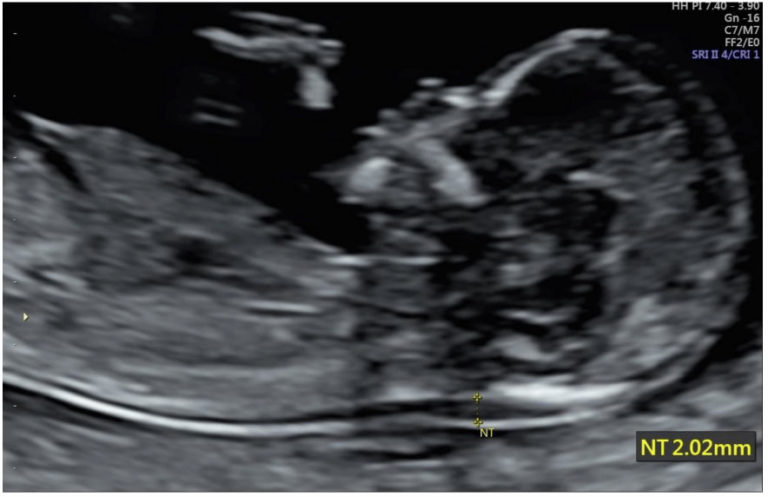

Measuring the nuchal translucency

The nuchal translucency is the fluid found at the back of your baby’s head and neck, just beneath the skin. The thickness of this fluid can be precisely measured; this is called the nuchal translucency (or NT) measurement. Normally the amount of fluid is small, producing a thin NT measurement.

We know that the amount of fluid can increase in the presence of certain conditions, producing a thicker NT measurement. Conditions associated with an increased NT measurement include some chromosome abnormalities (for example, trisomy 13, 18 and 21) and some structural problems (for example, heart abnormalities). An increased NT measurement does not always mean the baby has a problem but it does increase the risk. The NT measurement can also be used in the calculation for the Combined Screening result for Down syndrome (see First trimester combined Screening for Down Syndrome). For women who prefer to have the NIPT test for Down Syndrome Screening, it is still useful to have the NT scan performed as a way of helping to detect abnormalities in the baby and also helping to detect chromosomal problems which may not be detected by NIPT.

- An ultrasound scan which measures the nuchal translucency measurement (see image below) at 11+0 -13+6 weeks as well as assessment of the presence of the baby’s nasal bone and assessment of the baby’s anatomy.

Nuchal translucency: The nuchal translucency is the fluid found at the back of your baby’s head and neck, just beneath the skin. The thickness of this fluid can be precisely measured; this is called the nuchal translucency (or NT) measurement.